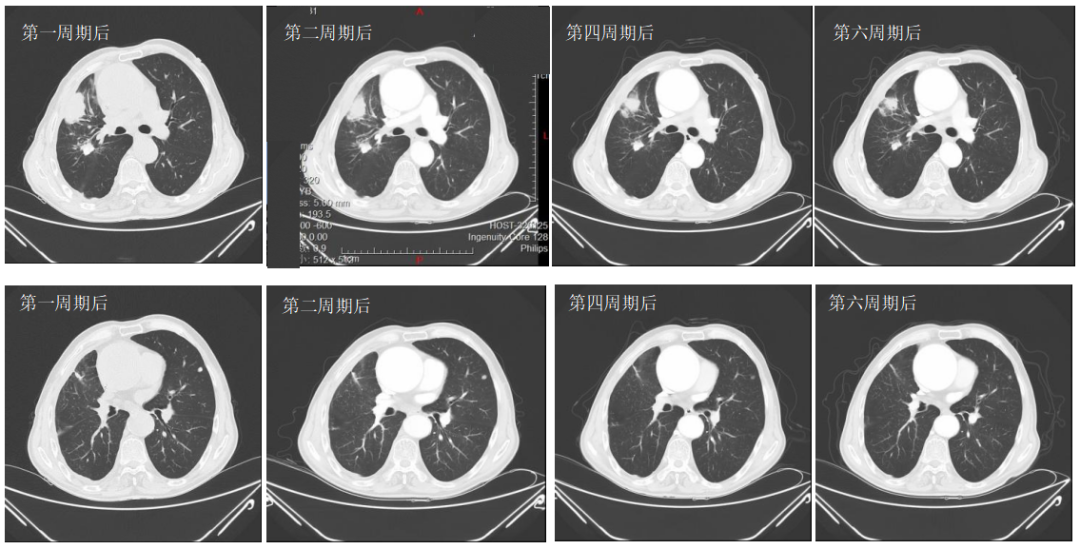

2022-07-01至2022-10-21行6周期斯鲁利单抗300mg d1+白蛋白紫杉醇(260mg/m2)450mg d1+奈达铂(75mg/m2)130mg d1,q21d治疗,同时给予伊班膦酸钠预防骨不良事件。期间因化疗后III度骨髓抑制,第5、6周期白蛋白紫杉醇+奈达铂双药减量10%化疗。

2022-08-15(治疗2周期后)CT、2022-09-28(治疗4周期后)CT、2022-11-08(治疗6周期后)CT:右肺上叶前段软组织密度影逐渐缩小(49mm*27mm→45mm*23mm→44mm*22mm),疗效综合评估SD。